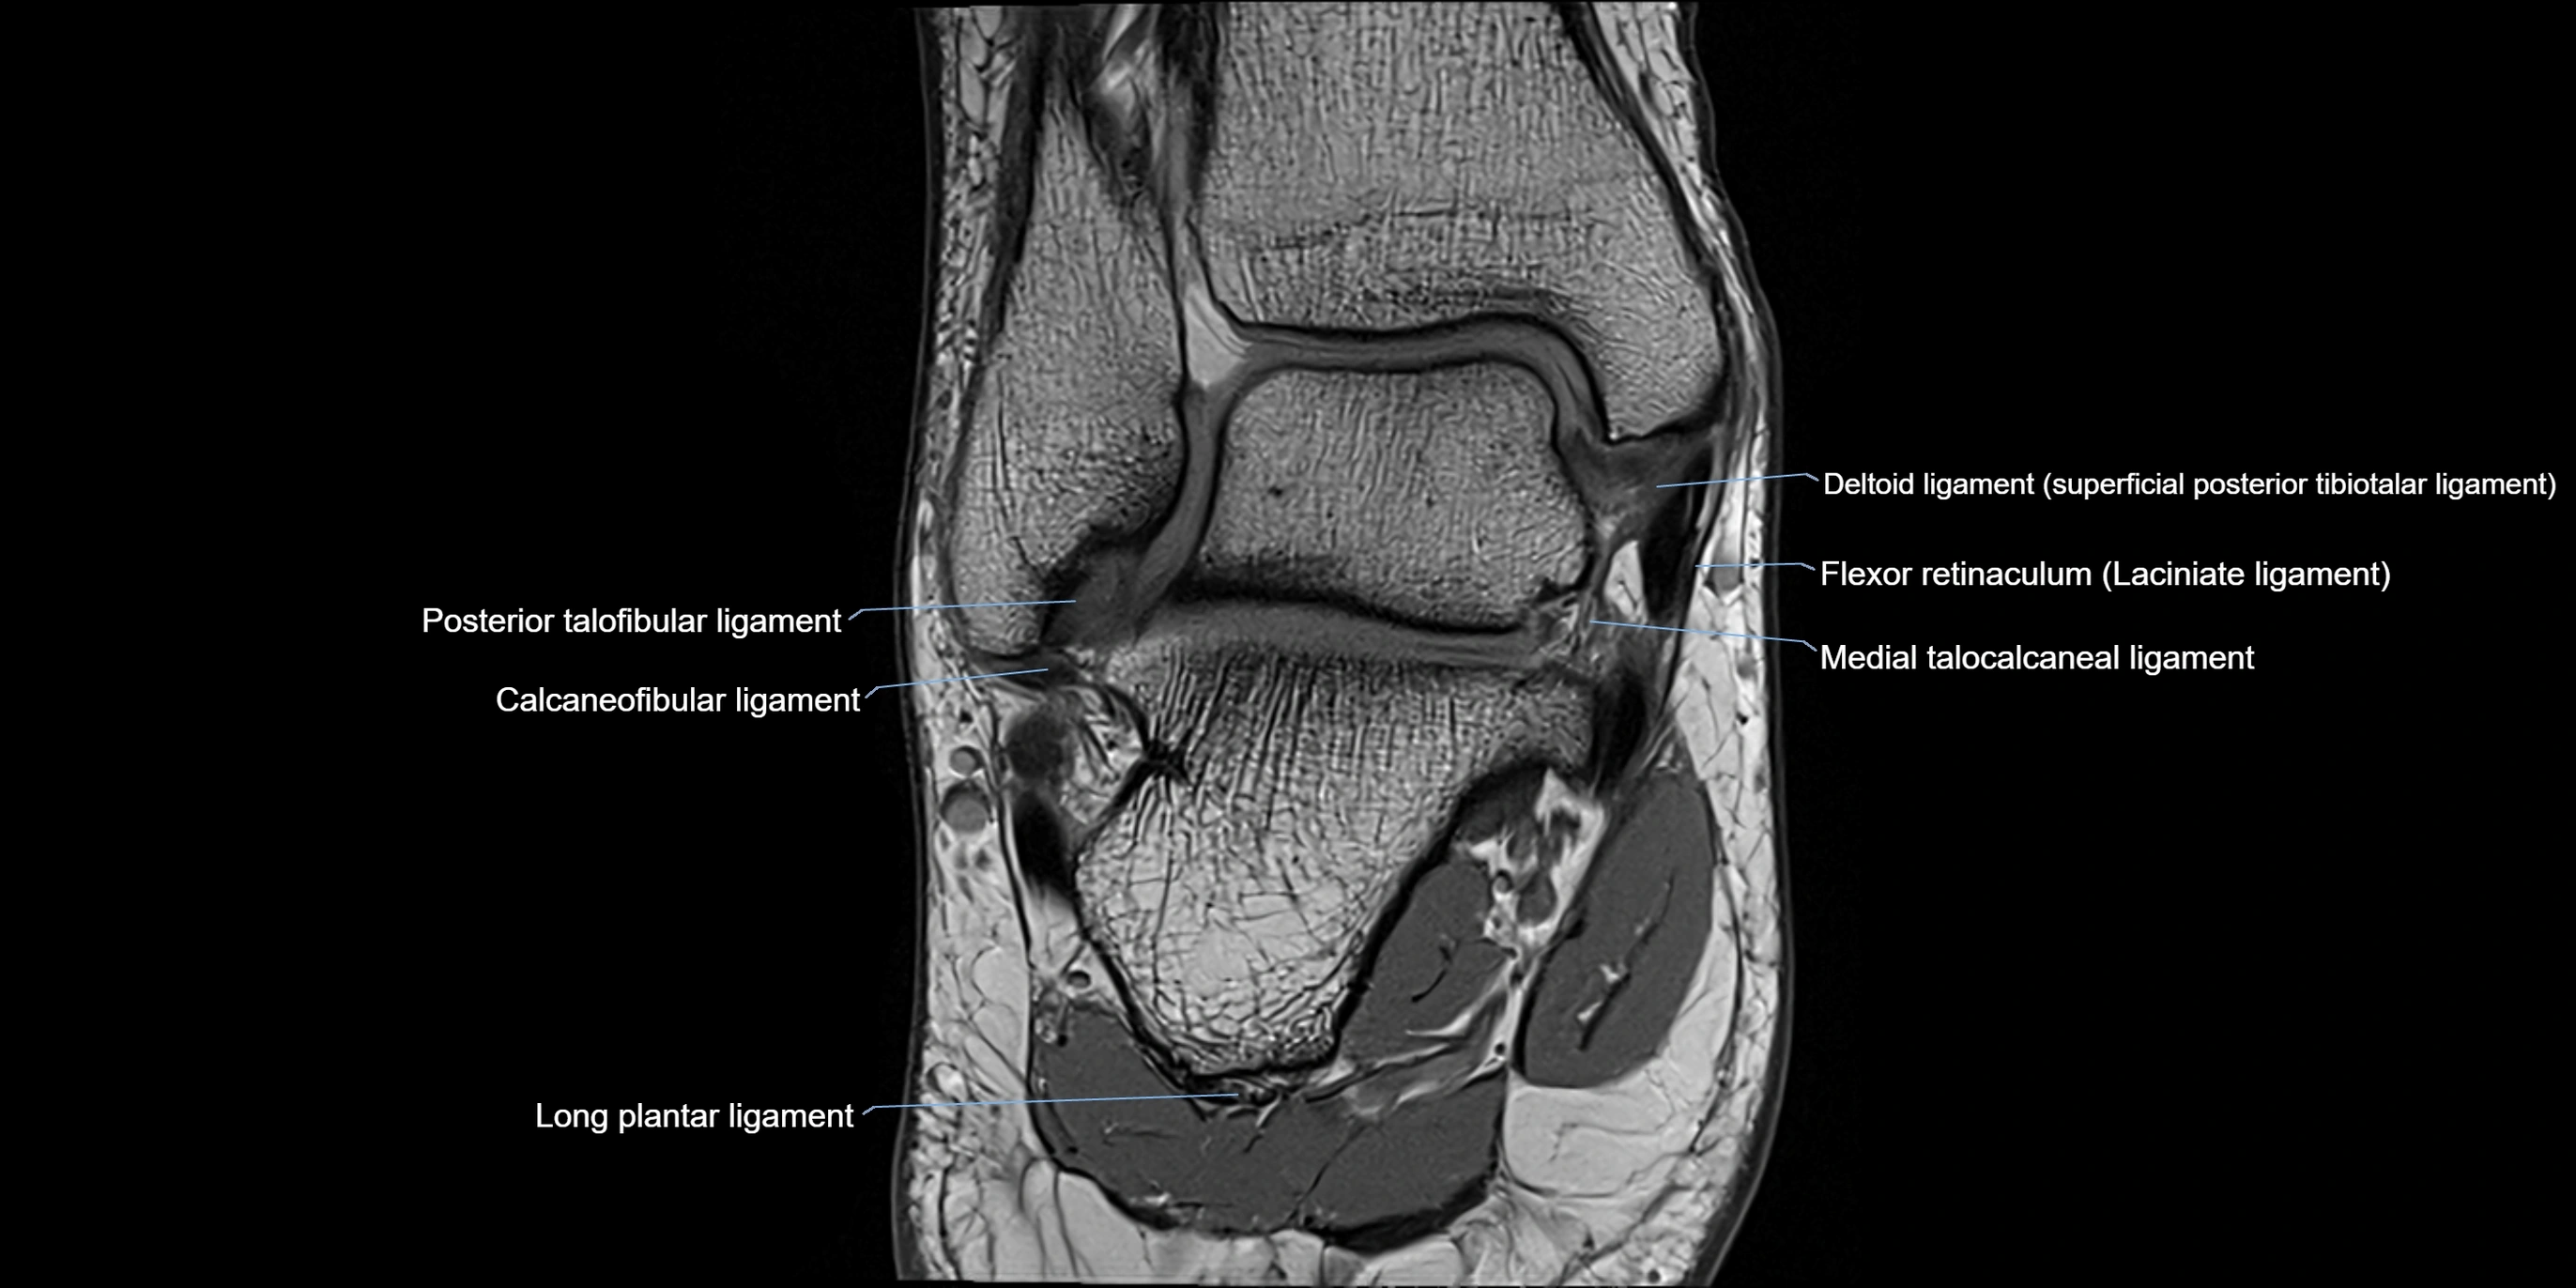

MRI image

image